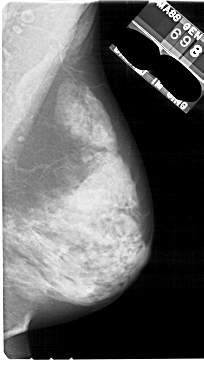

A_1844_1.RIGHT_MLO

RIGHT_MLO LINES 5491 PIXELS_PER_LINE 3046 BITS_PER_PIXEL 12 RESOLUTION 43.5 NON_OVERLAY